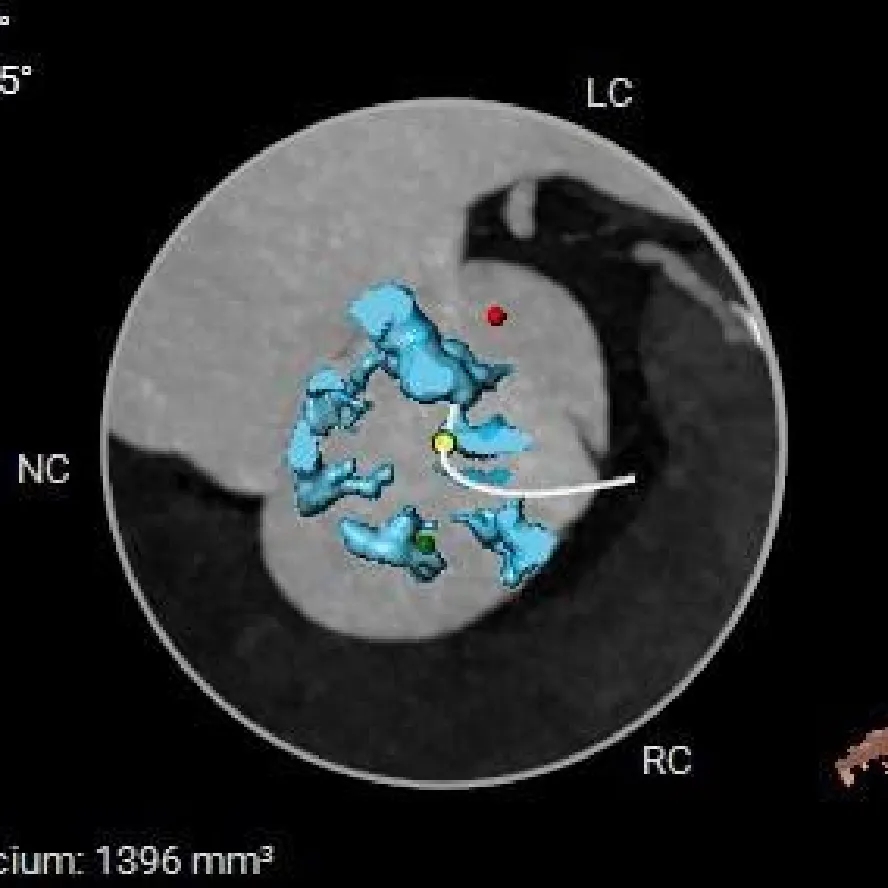

术前CT分析

TYPE-0型二叶瓣(纵列式),重度钙化,钙化分布不均匀,延伸至流出道可见,瓣叶明显增厚;

瓣环径约为24.0mm,流出道偏收口型,心室壁增厚,收缩期小心室;

主动脉根部测量

Annulus:24mm

LVOT:21.5mm

钙化积分:1396

SOV:30.6*43mm

STJ:41.9mm

AAO:51.2mm